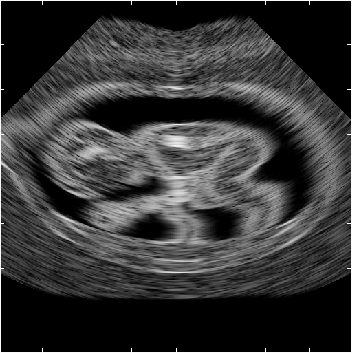

Calculation of B-mode image of synthetic fetus

A phantom for a 3 month old fetus has been made. 200,000 scatterers were randomly distributed within the phantom, and with a Gaussian distributed scatter amplitude with a standard deviation determined by the scatter map. The phantom was scanned with a 5 MHz 64 element phased array transducer with lambda/2 spacing and Hanning apodization. A single transmit focus 70 mm from the transducer was used, and focusing during reception is at 40 to 140 mm in 10 mm increments. The images consists of 128 lines with 0.7 degrees between lines.

The fetus image is shown below. Note how the anatomy can be clearly seen at the level of detail of the scatterer map. The same boundary features as for the kidney image is also seen.

The images have many of the features from real scan images, but still lack details. This can be ascribed to the low level of details in the bitmap images, and that only a 2D model is used. But the images do show great potential for making powerful fully synthetic phantoms, that can be used for image quality evaluation.

Artificial fetus in 12th week.